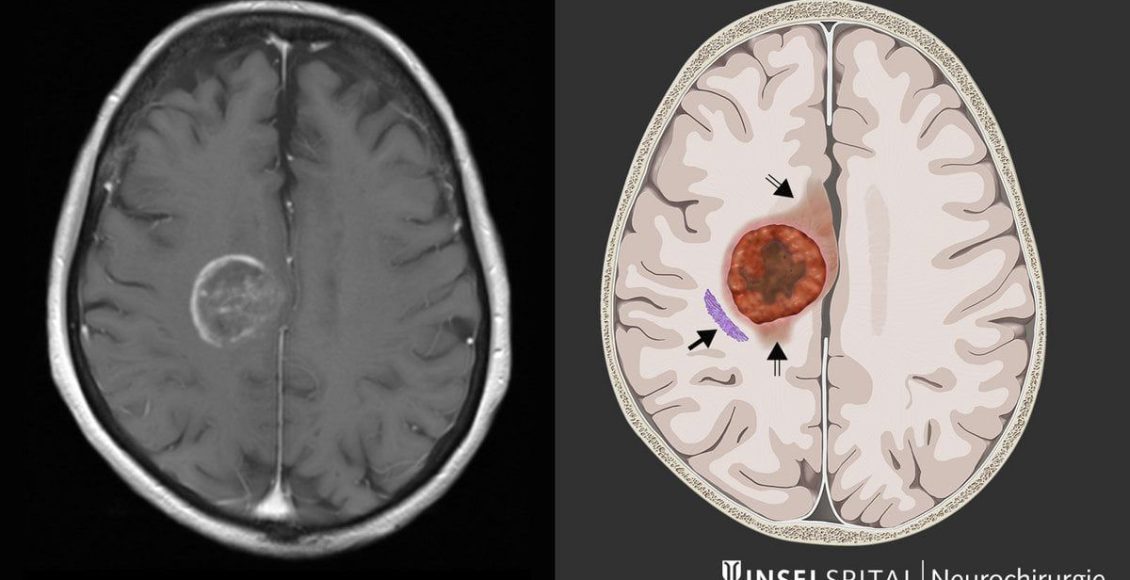

Des chercheurs de l’université du Michigan viennent de réaliser une importante découverte concernant le glioblastome, un cancer du cerveau aussi redouté que difficile à traiter.

Malgré les avancées de la chirurgie, de la radiothérapie et de la chimiothéraie, l’espérance de vie de ce cancer dépasse rarement deux ans après un diagnostic. Face à cette impasse, les scientifiques ont tenté une approche radicale : affamer la tumeur.

Dans un cerveau sain, les acides aminés servent de carburant pour assurer le bon fonctionnement des cellules. Mais chez les patients atteints de glioblastome, la tumeur détourne ces nutriments pour se multiplier. L’idée des chercheurs a donc été de priver la tumeur d’une partie de ces briques essentielles, afin de vérifier si sa croissance pouvait être freinée.

Les expériences ont été menées sur des souris atteintes de glioblastome, et les résultats ont dépassé les attentes. « Nous avons modifié l’alimentation dans les modèles murins et nous avons pu ralentir de manière significative et bloquer la croissance de ces tumeurs », a expliqué le Dr Daniel Wahl, oncologue à l’université du Michigan.

L’équipe s’est particulièrement concentrée sur deux acides aminés : la sérine et la glycine. Leur suppression a transformé la réponse des tumeurs aux traitements classiques. « Quand nous avons supprimé les acides aminés sérine et glycine chez les souris, leur réponse à la radiothérapie et à la chimiothérapie étaient meilleure et les tumeurs étaient plus petites que chez les souris témoins nourries avec de la sérine », a indiqué le Dr Deepak Nagrath, dans Science Daily. Cette stratégie, qui consiste à exploiter une faiblesse du métabolisme tumoral, pourrait bien marquer un tournant. En privant les cellules cancéreuses d’éléments essentiels à leur croissance,les chercheurs sont parvenus à les rendre plus vulnérables aux traitements existants. Une approche qui ouvre la voie à de nouvelles thérapies combinant régime alimentaire ciblé et protocoles médicaux.

Pour l’heure, cette découverte n’a été validée qu’en laboratoire mais l’équipe scientifique nourrit de grands espoirs/ »Nous pensons que cette vulnérabilité métabolique peur être exploitée et qu’elle pourrait changer la manière dont nous traitons ce cancer », ajoutent les chercheurs.

La prochaine étape est de vérifier su cette stratégie est applicable à l’humain. Des essais cliniques sont déjà envisagés afin de tester l’impact de régimes spécialement conçus pour réduire la sérine dans le sang. Si ces résultats se confirment, il s’agirait d’une avancée majeure dans la lutte contre l’un des cancers du cerveau les plus agressifs.